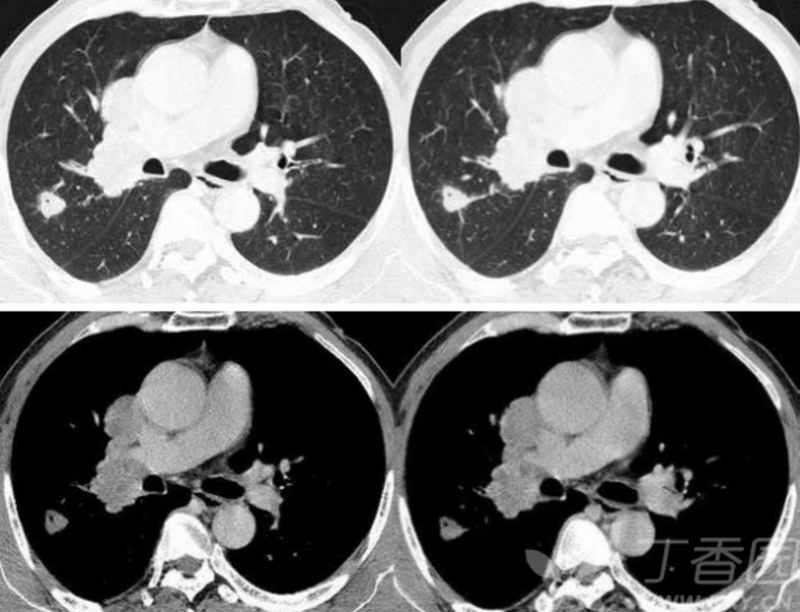

大叶性肺炎、肺水肿等急性渗出性病变其病理变化主要在肺泡,并不侵犯支气管,同时,急性渗出性病变病程相对较短,以渗出为主,此时肺实质的变化对支气管的影响较小,基本不足以引起其病变范围内支气管的形态和走行的改变,因此,其支气管充气征的表现为管腔未见明显改变,管壁光整,分支完整,走行柔软自然,即I型青枝型。I型青枝型所显示的支气管管腔未见明显改变,走行自然,整个支气管树柔软状如青树支,名为青枝型,这是肺炎C征象;Ⅱ型,所显示的充气支气管管腔以扩张为主,名为扩张型;Ⅲ型,显示支气管管腔狭窄与扩张并存,小分枝残缺而使支气管树形态不完整,支气管走行僵直,状如枯枝,命名为枯枝型;Ⅳ型,支气管充气征与支气管黏液征并存,名为复合型。

在大片肺实变病灶内的细条状空气密度影,或直径1mm的小泡状空气密度影,连续的几个层面都能出现,其支气管壁柔软,无僵硬感,分支自然,支气管径由粗变细;这是肺炎C征象。